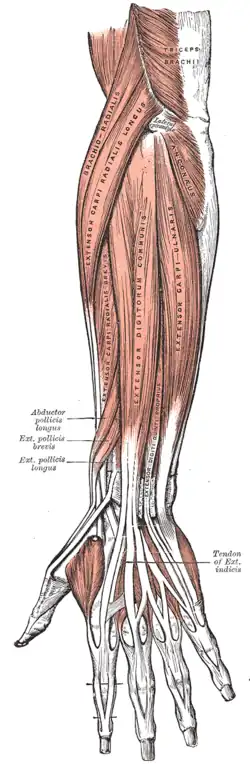

Superfície posterior do antebraço. Músculos superficiais.

Superfície posterior do antebraço. Músculos superficiais. -